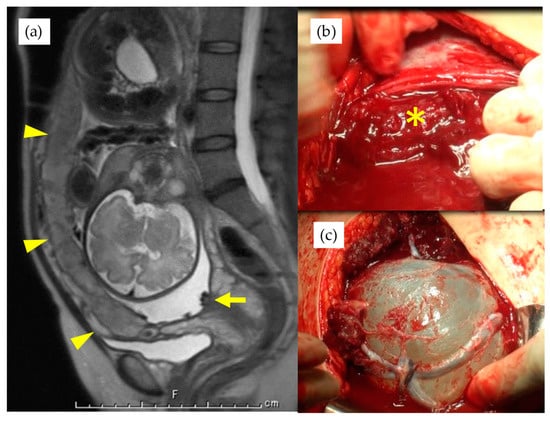

Figure 1. (a) magnetic resonance imaging of a case with the placenta covering whole anterior uterine wall, indicated by arrowheads, and arrow indicates fetal vessels covering cervical internal ostium. * indicates placenta after lateral extension of uterine incision (b) and the bleeding from the maternal vascular bed. Velamentous fetal vessels are visible on the amniotic membrane after the Ward technique (c).

The patients in this study, who were diagnosed with VP before 30th GW, were scheduled to be hospitalized between 30th–31st GW. Those with symptomatic uterine contraction and/or shortened cervix were hospitalized at any GW. After hospitalization, routine cardiotocogram (CTG) monitoring was performed twice a day (for about 40 min) for asymptomatic patients, and tocolytic treatment was started if any uterine contraction was observed within 10 to 15 min, even without pain or cervical shortening. The routine administration of antenatal steroids for fetal lung maturation was refrained from for stable cases. Cervical cerclage was considered for those cases with a shortened cervix less than 25 mm and recognized before 25th GW. A cesarean section (CS) was planned between 35–36th GW for cases where expectant management was possible. If the VP diagnosis was made after 30th GW, the patient was admitted soon after the diagnosis and, if the diagnosis was made after 36th GW, the CS was scheduled immediately. Before the CS, the operation team, including well-experienced obstetricians, performed meticulous pre-operational mapping for placental and fetal vessels with TA- and TV-US, especially at the site where the uterine incision was to be made. For those cases with an anteriorly located placenta covering the incision site, the Ward technique was planned to avoid injury to the placenta (Figure 1) [12,13]. Routinely, in cases where fetal vessels course just beneath the anterior wall, we first hold and lift the fetal presenting part with the intact membrane after the lateral elongation of the myometrial incision. The membrane is then ruptured, thus avoiding injury to the fetal vessels [14]. The final determination of the particular VP type is based on the findings at delivery and subsequent macroscopic examination of the placenta. In this study, the placental types for VP were evaluated as follows: type 1, a velamentous cord insertion into the placenta [1]; type 2, a multilobed or succenturiate placenta with fetal vessels connecting the placental lobes [1]; type 3, vessels branching out from the placental surface and returning to the placental cotyledons in a “boomerang orbit” [6,10]. The two cases with type 3 VP reported previously were also included in this study [10]. The VP patients were divided into two groups for statistical analysis to elucidate the clinical differences between the groups: the type 1 group included type 1 VP patients, and the non-Type 1 group included those patients with either type 2 or type 3 VP placentas. The standard deviation of birth weight was calculated using software from the Japanese Society for Pediatric Endocrinology (http://jspe.umin.jp/taikakubirthlongcrossv1.xlsx; downloaded on 1 March 2021).

Table 3 shows the results of management and operative outcomes. In 31 cases (56.4%), including three twin pregnancies, tocolytic therapy was necessary (ritodrine hydrochloride and/or magnesium sulfate), and a steroid for fetal lung maturation was given in 9/13 cases (69.2%) delivered before the 34th GW. An abnormal fetal heart rate pattern without uterine contractions was detected in one case in the type 1 group, and this case exhibited a relatively thick artery near the internal ostium (Figure 2). Cervical cerclage via the McDonald technique was performed in two cases in the type 1 group. One of these cases was a singleton pregnancy at 20th GW and a cervical length of 2.1 cm, delivered by CS at 33rd GW. The other was a monochorionic-diamniotic pregnancy case at 20th GW and a cervical length of 1.7 cm, delivered by CS at 31st GW; this patient had a previous history of preterm singleton delivery at 34th GW. Blood flow of fetal vessels was confirmed post-cerclage in both cases (Figure 3). Resolution was observed in 12 cases (21.8%) in total. An emergent CS was performed in 25 cases with increased uterine contractions and in one case with an indication of hypertensive disorder of pregnancy; none of these cases experienced the premature rupture of membranes. Although the Ward technique was more frequently used in the non-type 1 group, the details as to operative outcome showed no significant difference between the two groups. The transection of the placenta to approach the fetus was not used in any of the cases. All cases underwent a cesarean section, even in those cases of resolution of VP.

It has been rarely discussed as to the appropriate incision site of the uterine wall depending on the location of these vessels. Except in cases where placental invasion into the myometrium was suspected, we did not change the uterine incision site regardless of where the placenta was located and/or the fetal vessels coursed in pre-operational mapping. This technique was first introduced by Ward for cases with anterior placenta previa [12] and has recently shown to be safely applied in a study of a larger population [13]. We consider that the Ward technique for anterior placentation, and partially the ‘en caul’ technique for the anterior coursing of fetal vessels, might be also safely and successfully applied for VP cases.